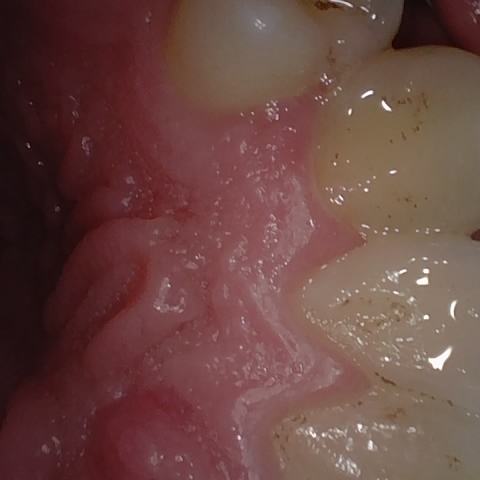

NHD39969

Annotated as "Good"

Original Image Rendering Image